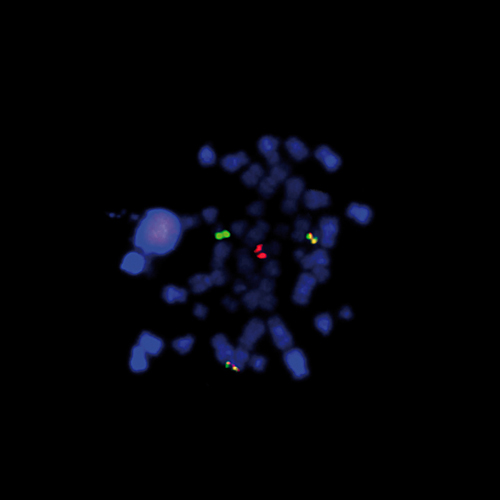

Malignant Melanoma: Immunohistochemistry staining of S-100B scanned using the Aperio AT2. Nuclear and cytoplasmic staining in tumor cells. S-100B: clone EP32

Clone EP32 was raised against S-100 beta protein. Immunoreactivity was observed in neuroectodermal tissue e.g. melanocytes, nerve fibres, dendritic cells, adipocytes and a percentage of macrophages, lymphocytes and plasma cells.